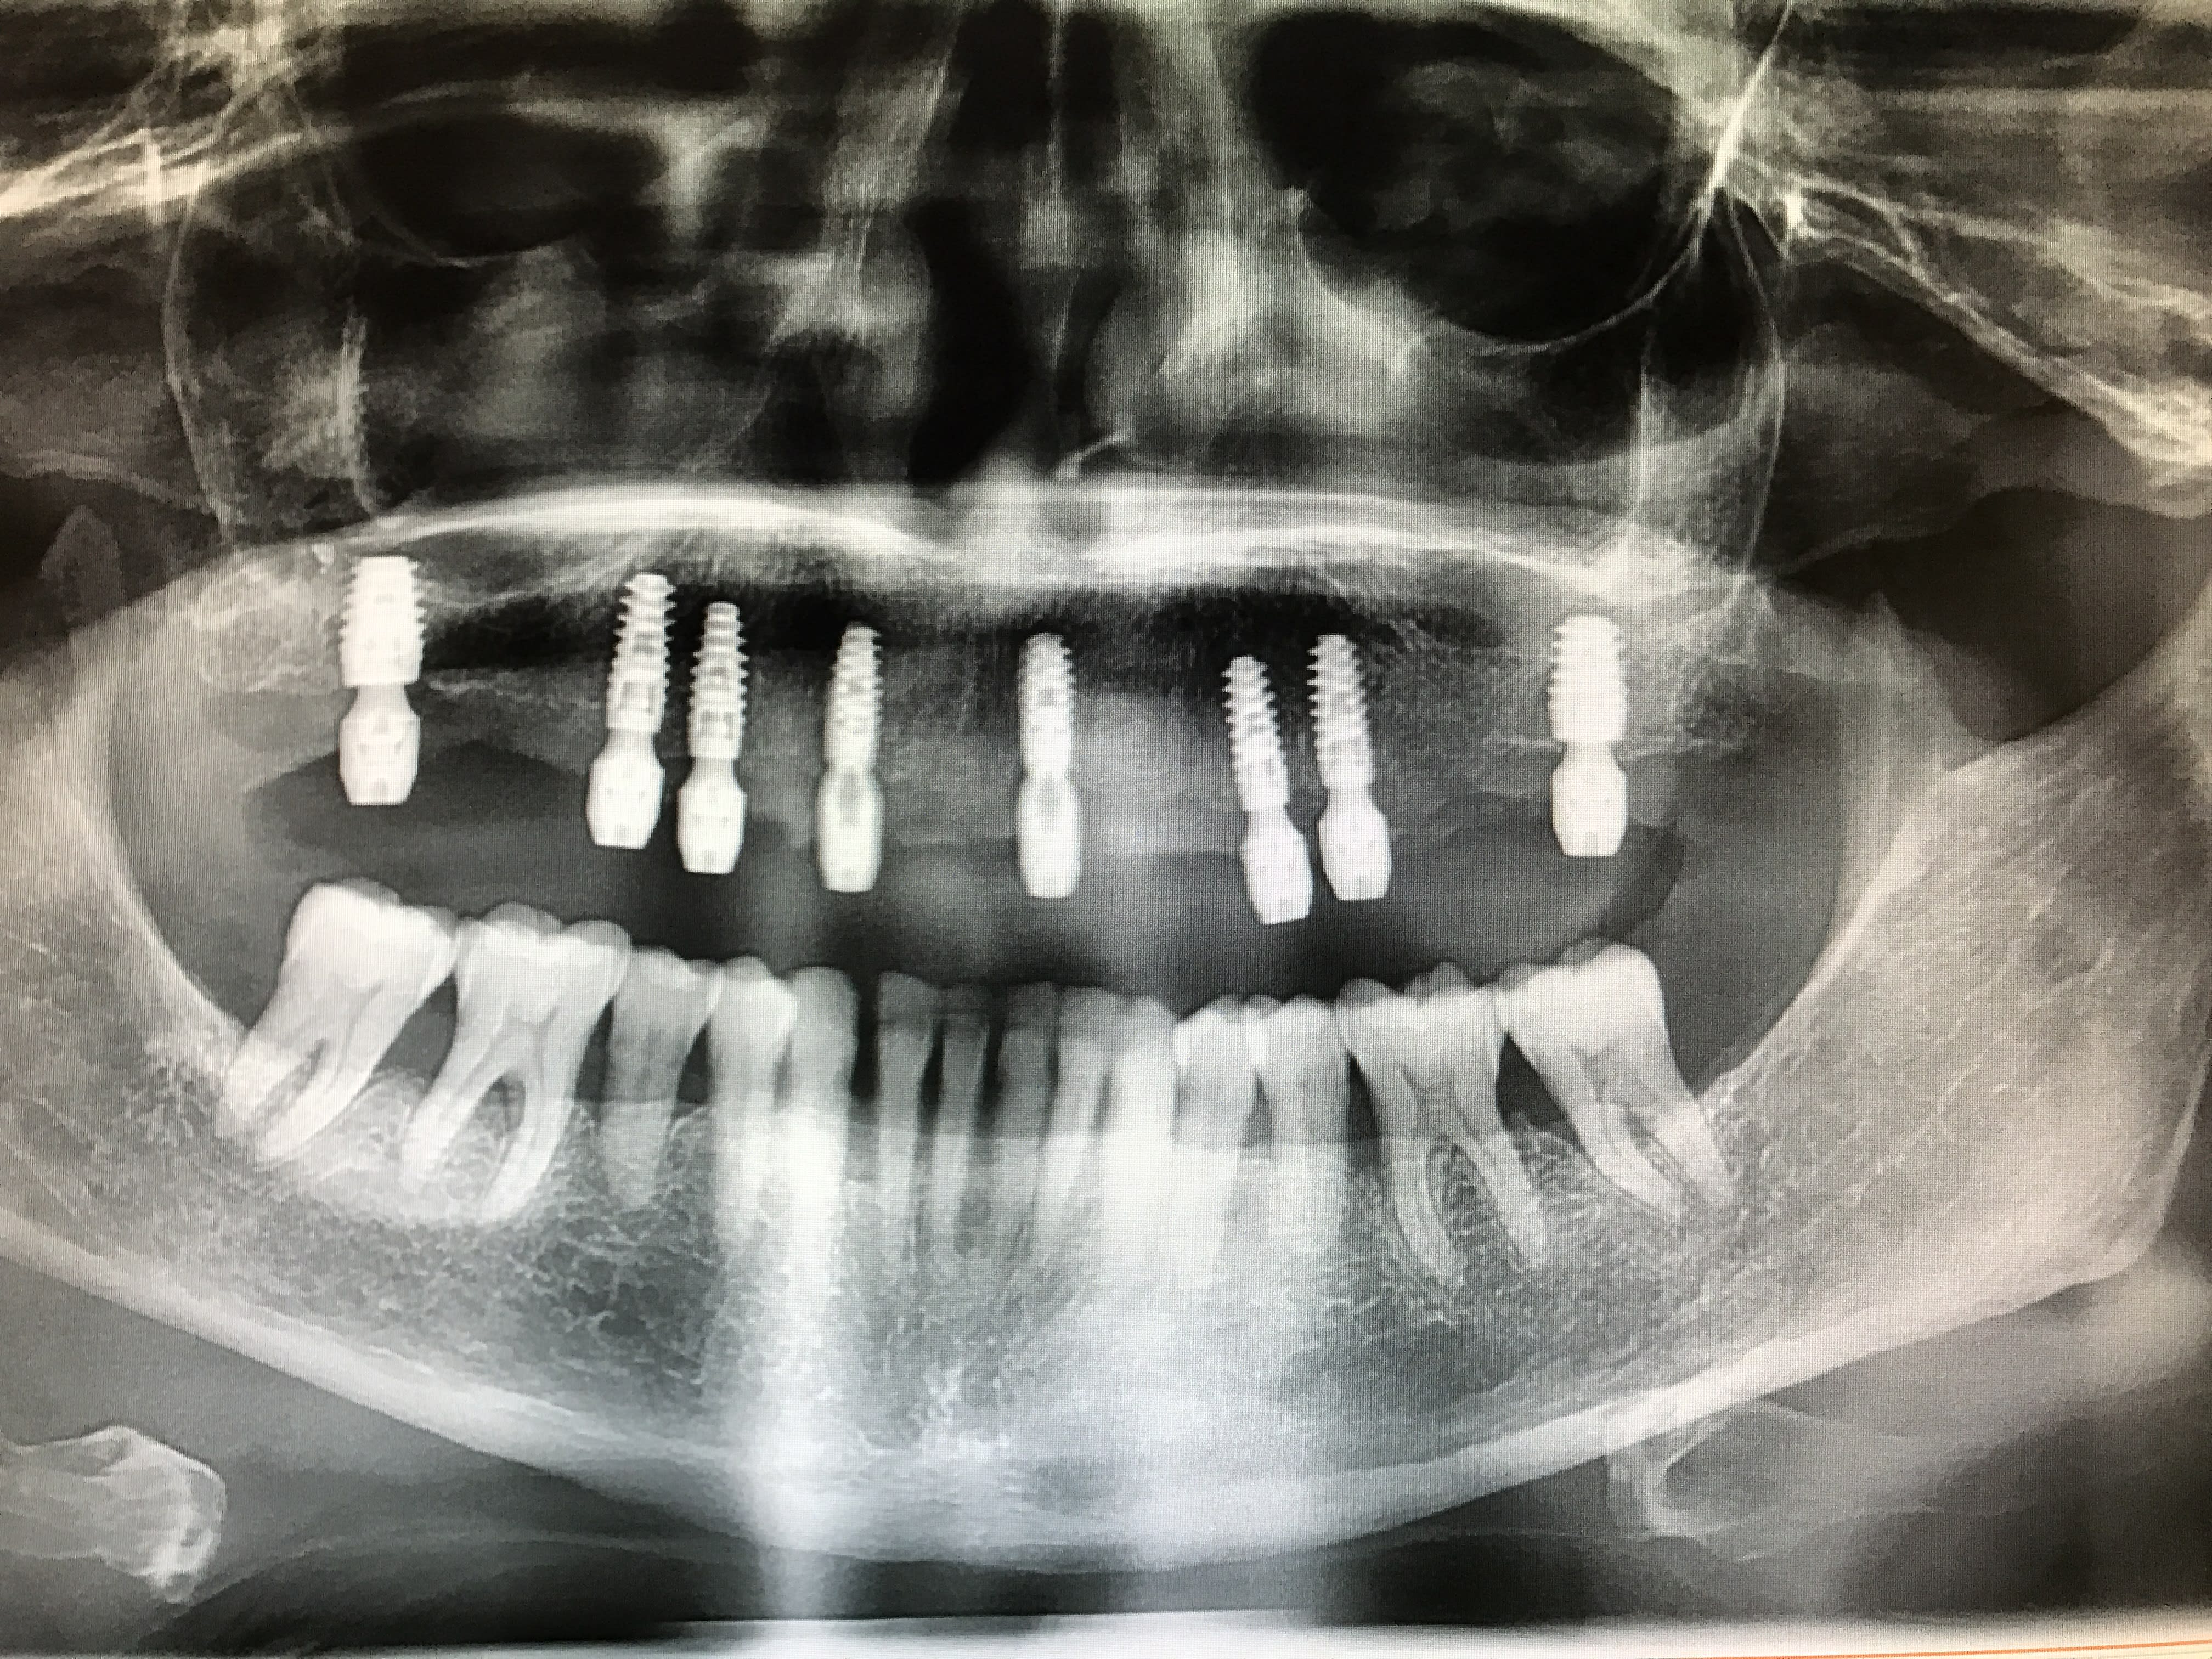

C'est mon premier cas de mise en charge immédiate.

Patient de 82 ans, sous préviscan, INR autour de 2,5 toute l'année.

Nous avons décidé avec le patient de faire une arcade courte (16-26) sur 6 implants. Une fois le haut validé, nous ferons le bridge 32-42 sur 2 implants + le remplacement de la 36.La 48 est à extraire et la 38 à voir.

J'ai demandé un guide radio simulant le future bridge avec des trous dans lequel j'ai mis du cavit (radioopaque). Ce guide est utilisé par la suite pour me repérer la position des premiers forages.

J'ai fait une simulation des implants avec CBCT. J'ai prévu utiliser Anthogyr axiom PX: 10mm de long, 4,6mm en postérieur et les 4 autres en 4mm.

Lors de la pose, l'assistante s'est trompé d'implant (et avec le stress je ne l'ai pas vérifié) pour le 24 (4,6 au lieu de 4mm). Je m'en suis rendu compte au moment de la 16 (plus de 4,6 en PX..) j'ai mis un 4,6 mais en REG, avec un blocage à 25N.

Ensuite la pose des piliers MU, droit standards sauf pour la 13 où j'ai du en poser à 20 degrés angulé pour suivre la crête antérieure bien résorbée.